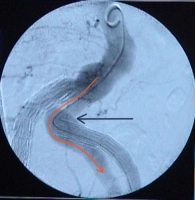

Endoleak Typ Ia: Fehlende Abdichtung der proximalen Landungszone durch Dislokation des Endografts der A. iliaca interna links